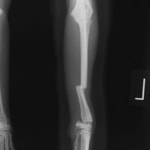

症例3:キルシュナーワイヤーのピンニングによる整復

ペルシャ猫 11ヶ月齢 雄

他院にて左大腿骨遠位の成長板骨折(salter-harrisⅠ型)が認められており、治療相談を目的として来院。当院にて、キルシュナーワイヤーを用いたピンニングにより骨折部位の整復を行いました。術後の経過は良好で、現在も経過観察中です。

術前レントゲン